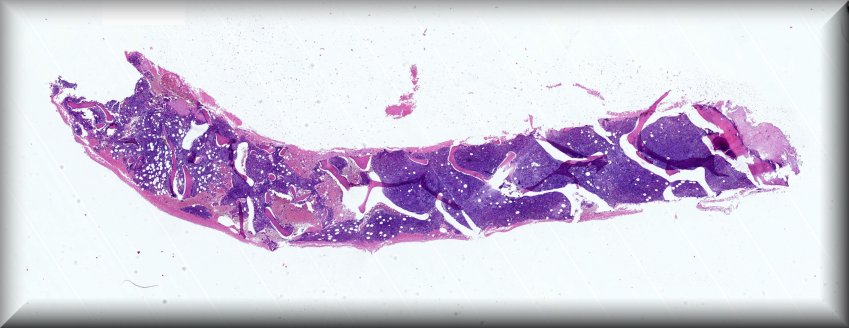

Caso 8.- Carmen Medina Medina, Alba Sánchez Martin, Víctor Carlos Puglia Santos, Pedro César Navarro Conde, Ana Isabel Jiménez Sánchez.

Hospital Arnau de Vilanova. Valencia

Varón de 74 años que acude a urgencias por astenia y disnea a esfuerzos moderados de 7 días de evolución, con pérdida de 10 Kg de peso y dolor lumbar, en el último mes. No fiebre, ni síntomas B acompañantes.Hemograma: Hematíes: 2,65 x10^12/L; Hemoglobina: 8,00 g/dL. Leucocitos: 0,94 x10^9/L; Neutrófilos: 8,40 %; Linfocitos: 71,30 %; Monocitos: 16,00 %; Eosinófilos: 0,00 %; Basófilos: 0,00 %. Plaquetas: 22 x10^9/L. Ingresa para estudio de pancitopenia.